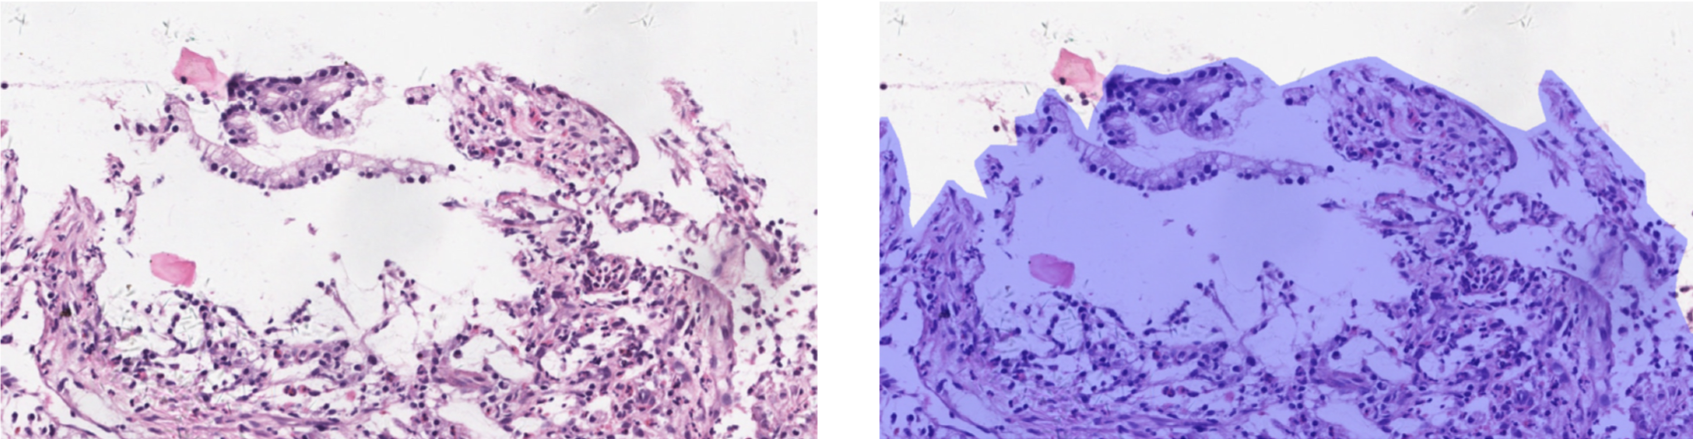

Refer to caption

Figure 7: Examples of segmentation results. We show 555 ROIs with their original image (left) and the ground truth masks (right) labeled by pathologists. Results of our proposed method and other comparison methods are illustrated in the middle columns.

To better demonstrate the effectiveness of our proposed method, we show some examples in Figure. 7. FCN and U-Net often generate unclear and unsmooth boundaries (1st and 2nd row). As we could see from the 3rd to the 5th column, the 3 comparison methods make a lot of false positives compared to our method. In the 2nd row, U-Net even includes red blood cell area in the result. In the 5th row, our model is the only one that successfully identifies the tissue on the bottom to be negative.